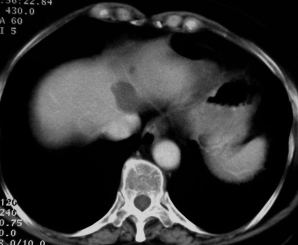

scanner 70 S après injection  Scanner 70 S après injection

Ce patient est porteur d'un angiome du lobe gauche et d'une métastase du lobe droit. Le signal des deux lésions est identique en scanner et Imagerie T2. La métastase a cependant une forme plus irrégulière qui doit attirer l'attention.